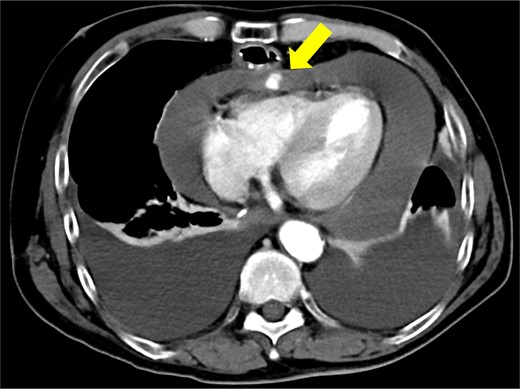

Immediately prior to surgery, he suffered cardiac arrest requiring cardiopulmonary resuscitation but recovered quickly, and a median sternotomy was performed expeditiously. Fortunately, no injury to the retrosternal gastric tube occurred. The gastric tube was pushed into the right thorax to expose the pericardial surface. A pericardial hematoma was observed, and pericardiotomy relieved the tamponade. Removal of the hematoma revealed a 5 mm aneurysm in the peripheral right ventricular branch with pulsatile bleeding (Fig. 4). Hemostasis was achieved using horizontal mattress suturing between the central and peripheral areas of the aneurysm without bypass grafting to the right ventricular branch artery by cardiac surgeon. In addition, TacoSeal® (CSL Behring, Pennsylvania, USA) and Volheal® (KM Biologics, Kumamoto City, Japan) were applied (Fig. 5). The operative time was 133 min, with a blood loss of 1160 ml. Oral intake was initiated on POD 5, and the patient was discharged on POD 22 with an unremarkable postoperative course.

A 5 mm aneurysm in the peripheral right ventricular branch with pulsatile bleeding is observed.